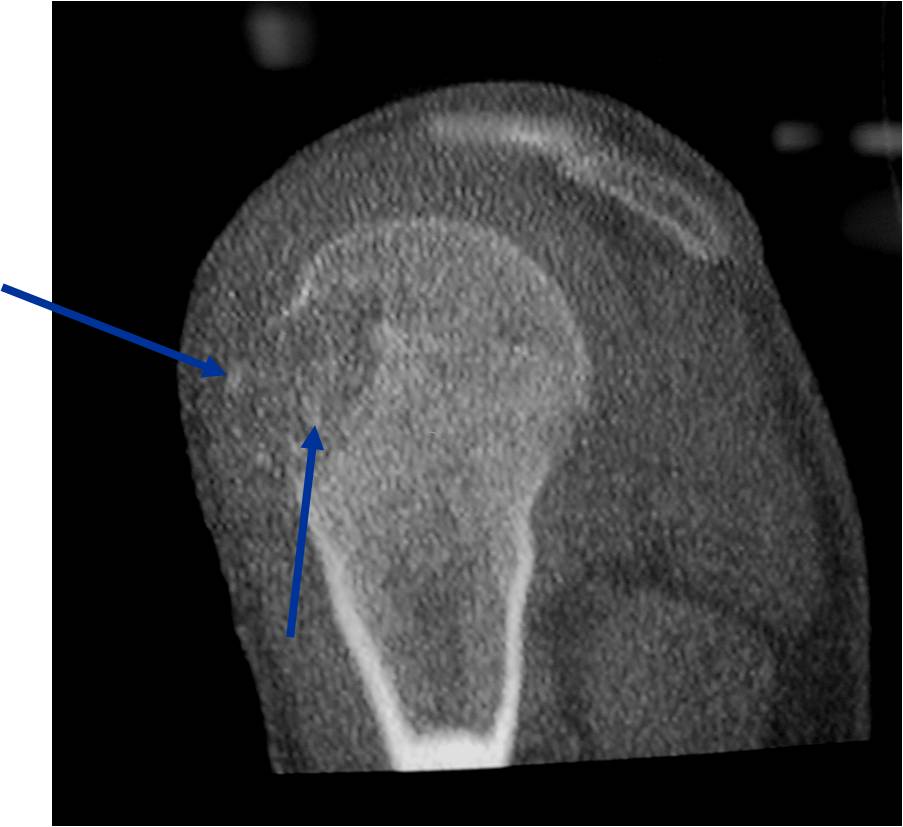

- (CT appearance)

- Most useful for detecting subtle mineralization not apparent on X-rays

- Useful for identifying intact periosteum around any expansile soft tissue component

- surrounding thin reactive shell of bone/mineralization (Egg Shell Rim of Calcification)

- helps place the tumor in a benign category

- helps evaluate:

- bony quality

- extent of bone and cortical destruction

- whether the subchondral plate of bone adjacent to the articular cartilage has been destroyed or is intact